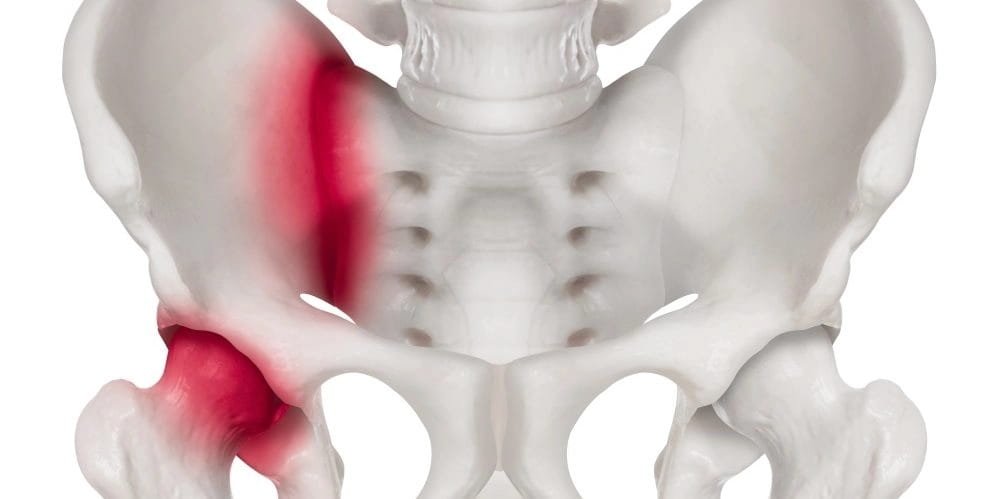

6. Рак тазовых костей

Раковые поражения костей таза также приводят к тупой боли в копчике, а иногда болит возле копчика. Оно чаще всего является вторичным и развивается по причине метастазирования основного опухолевого образования. На кости таза рак в большинстве случаев переходит с органов малого таза, брюшной полости и мягких тканей нижней части тела.

В редких случаях рак таза может появляться как самостоятельное заболевание, при котором злокачественные клетки развиваются непосредственно в костной ткани. У больного при этом могут быть диагностированы такие виды болезни: остеогенная саркома, остеобластоклестома и паростальная саркома. Среди всех онкологических поражений первичный рак костей занимает не более 1%, а непосредственно таза – еще меньше. В то же время такая форма болезни является крайне тяжелой и опасной из-за полной скрытости патологии в начальных стадиях и особенно стремительному развитию.

Основными симптомами опасной болезни, которые, к сожалению, появляются только на 3, а иногда и 4 стадии, являются:

• боль в районе копчика ноющего характера, которая присутствует постоянно и регулярно приступообразно усиливается и имеет четкое иррадиирование в копчик;

• резкое снижение подвижности нижних конечностей;

• боли в животе неясного характера;

• беспричинная тошнота;

• сильная слабость;

• резкое снижение веса;

• стойкое повышение температуры.